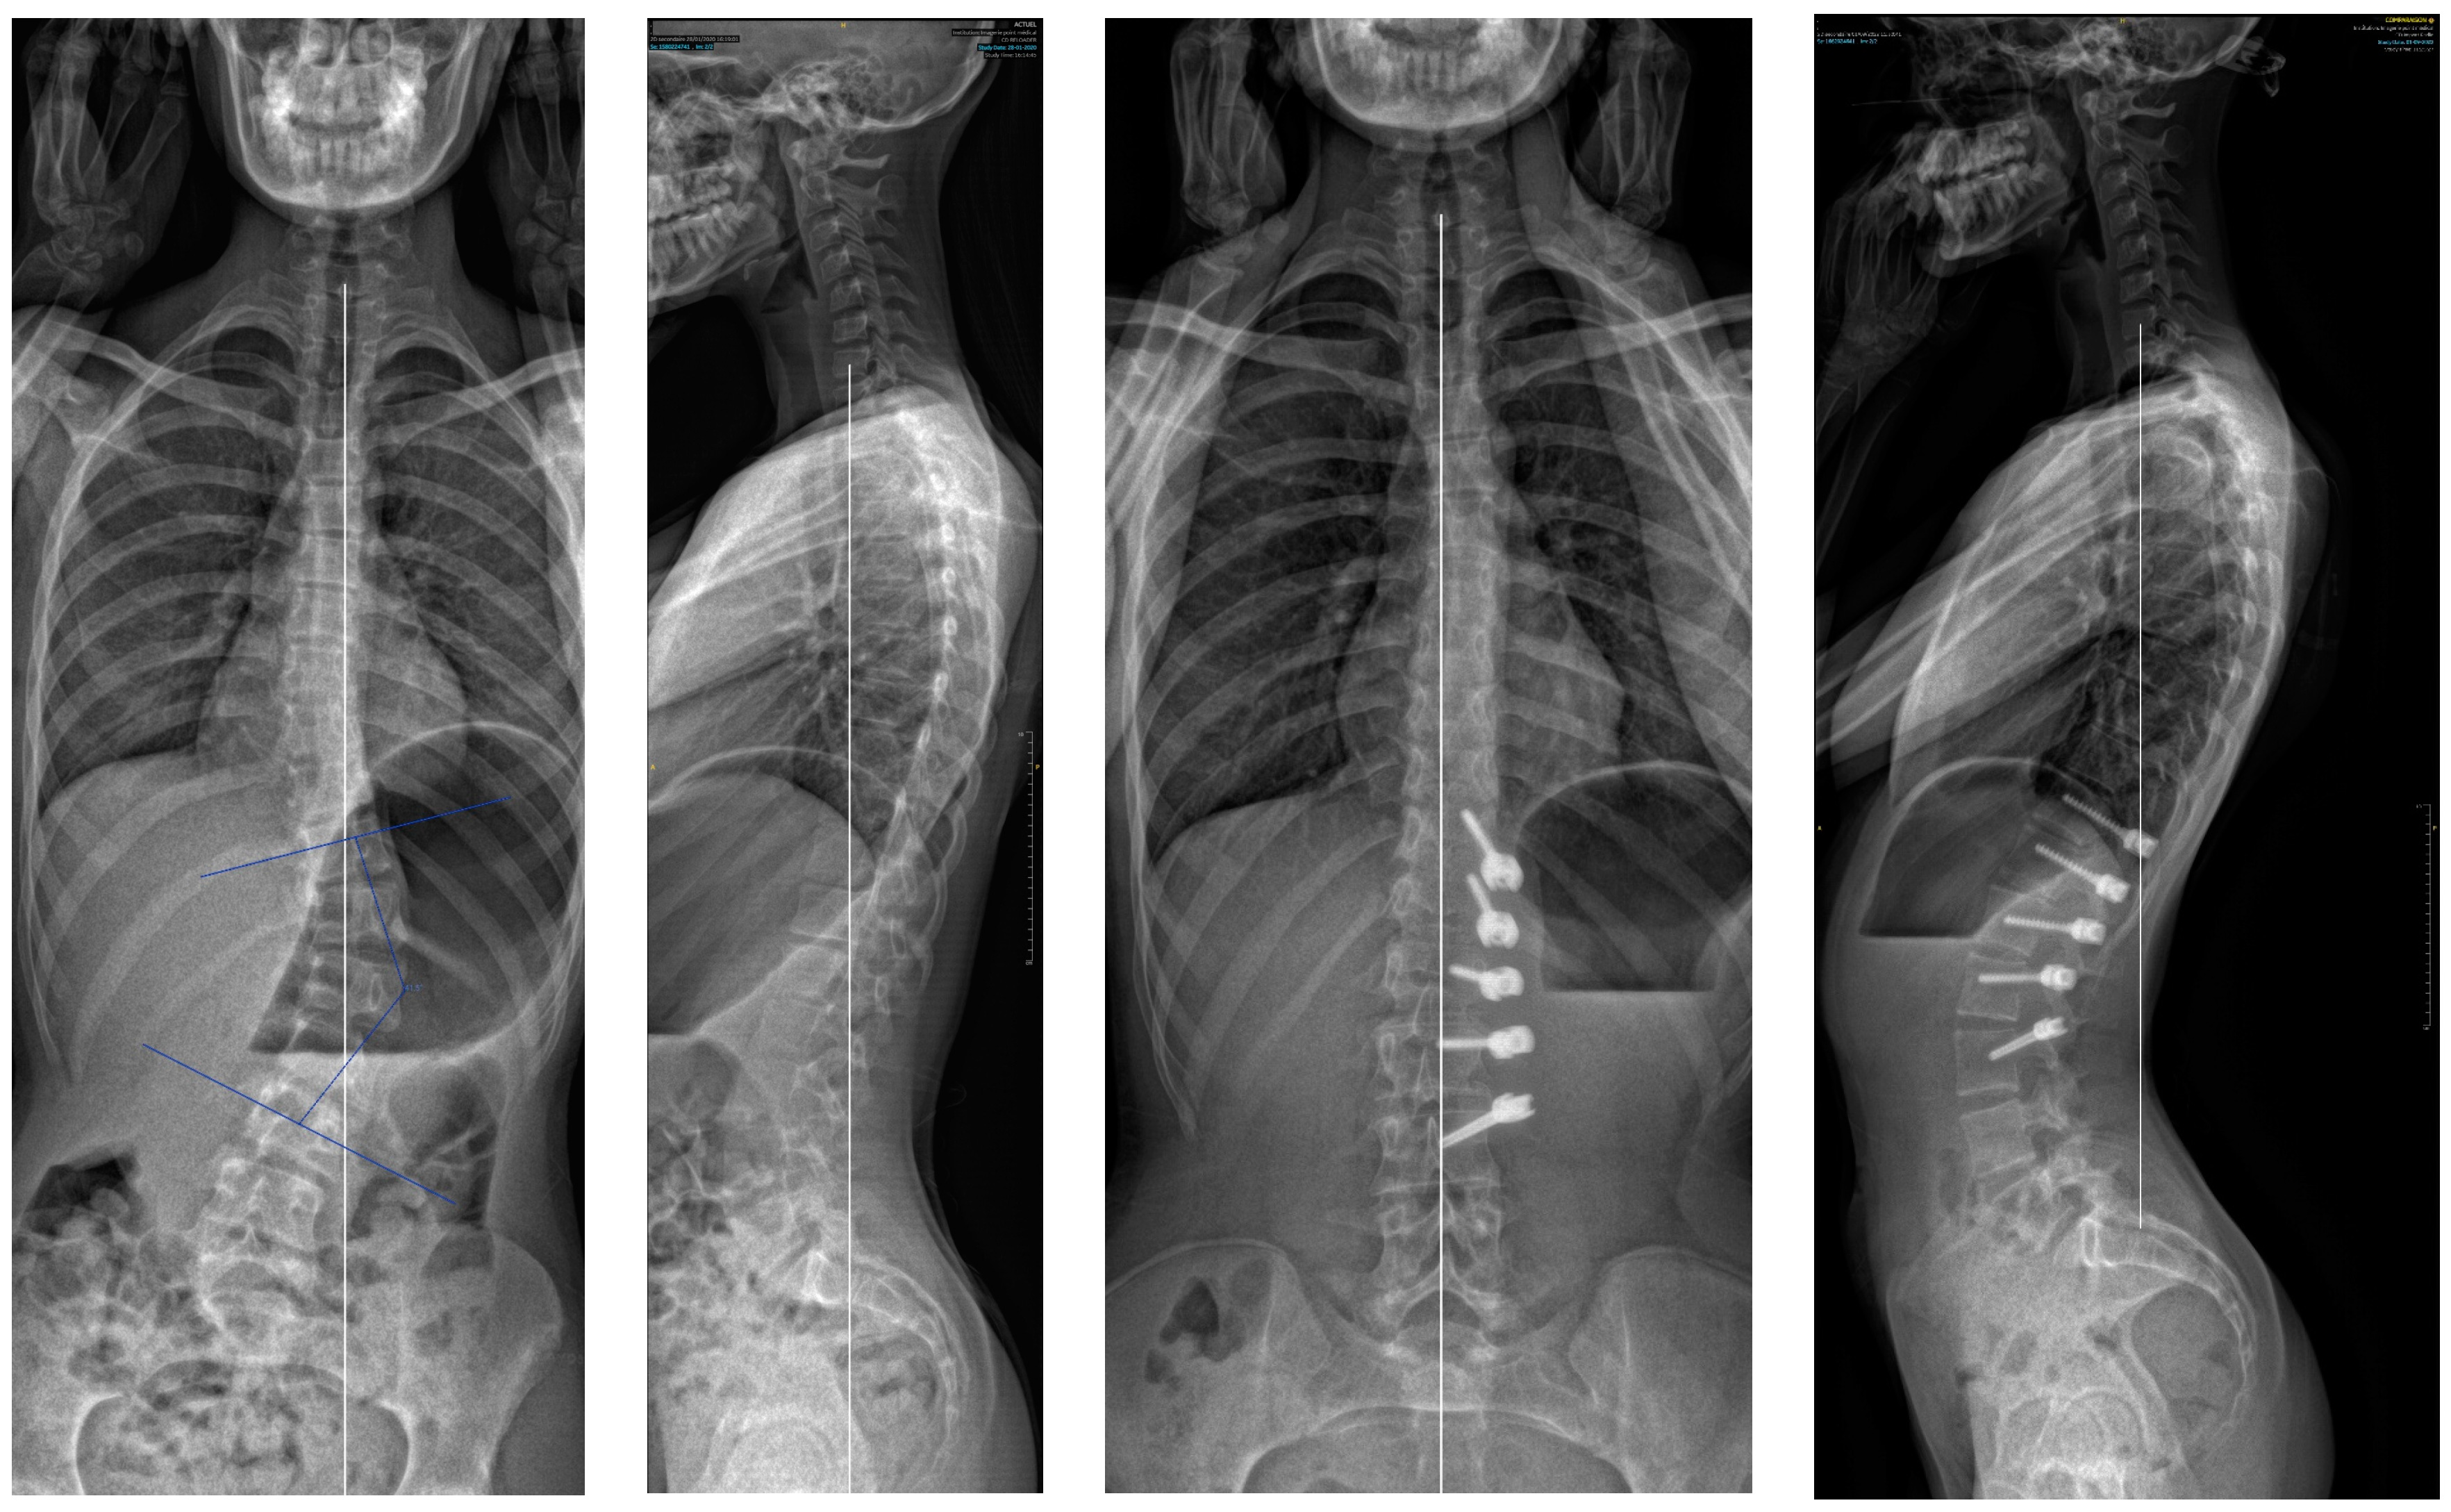

2.2. Surgical Technique

3. Results

| Major curve | 43.9° (9.2) | 20.3° (16.2) | 13.2° (28.2) |

| Secondary curve | 29.1° (12.6) | 21.9° (11.2) | 19.9° (13.9) |

| Kyphosis (T4T12) | 23.2° (7.8) | 25.1° (9.5) | 26.9° (12.6) |

| Lordosis (L1L5) | 41.7° (7.8) | 42.4° (10.1) | 42.8° (7.5) |